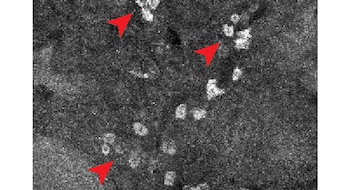

Según el artículo, “vCATCH ofrece imágenes de fármacos a resolución celular en todo el ratón adulto”, lo que representa una mejora respecto a los métodos previos que solo alcanzaban secciones finas de tejidos. Los experimentos demostraron que ambos medicamentos se distribuyen ampliamente en órganos como hígado y tracto gastrointestinal, aunque presentan patrones distintos en tejidos específicos.

La investigación también identificó diferencias en la distribución dentro de los órganos. Por ejemplo, afatinib se encontró sobre todo en los glomérulos, que son los filtros microscópicos del riñón encargados de limpiar la sangre. En cambio, ibrutinib se acumuló en los túbulos de la corteza renal, estructuras responsables del procesamiento y transporte de las sustancias filtradas por el órgano. Estos resultados sugieren que la unión de los fármacos puede involucrar tanto efectos terapéuticos como efectos colaterales, ya que alcanzan tipos celulares no previstos inicialmente.

El trabajo consistió en administrar versiones modificadas de los fármacos a ratones vivos para permitir su distribución natural y, tras un tiempo, procesar tanto los órganos extraídos como el cuerpo entero del animal (retirando la piel) con sustancias que los vuelven transparentes para facilitar el marcaje químico. Luego, emplearon microscopios especiales de hoja de luz capaces de captar imágenes en tres dimensiones y programas de inteligencia artificial que ayudaron a identificar y contar las células marcadas.

Para comprobar que la técnica era confiable, los investigadores hicieron pruebas en tejidos que ya se sabía que contenían las proteínas a las que se unen los medicamentos. Además, utilizaron ratones sanos para comparar la distribución normal de los fármacos en el cuerpo. Así lograron identificar con precisión en qué partes del organismo y en qué tipos de células se encontraban los medicamentos, como en células del hígado, células del sistema inmune y células del riñón.